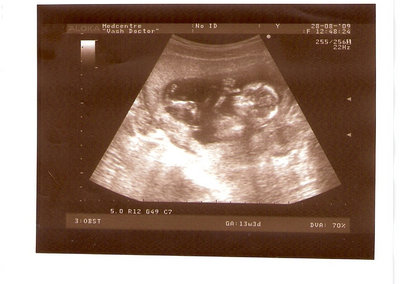

СЫН

| Вложения: |

2.jpg [ 110.14 КБ | Просмотров: 2437 ]

13 НЕД И 5 ДНЕЙ

3.jpg [ 96.81 КБ | Просмотров: 2435 ]

Nikisa писал(а): Foto prosto chudesnoe. A na kakom sroke uznali, chto sin.............. НА 13 НЕДЕЛЯХ.КАК РАЗ ВОТ В ЭТО узи, ОНО УМЕНЯ ВТОРОЕ БЫЛО. ЭТО КОНЕЧНО МАЛЕНЬКИЙ СРОК ДЛЯ ОПРЕДЕЛЕНИЯ ПОЛА. НО Я ПОПРОСИЛА ВРАЧА(ЭТО КТСТАТИВ РОССИИ БЫЛО) ХОТЯ БЫ ПРЕДПОЛОЖИТЬ. ЕЙ ВСЁ ТАКИ УДАЛОСЬ РАССМОТРЕТЬ.НУ ВООБЩЕМ ЧЕРЕЗ НЕСКОЛЬ ДНЕЙ ПОЙДУ К ВРАЧУ, УЖЕ АМЕРЕКАНСКОМУ И УЗНАЮ ТОЧНО. К ТОМУ ВРЕМЕНИ У МЕНЯ БУДЕТ СРОК 18 НЕДЕЛЬ. ХОТЕЛОСЬ БЫ ПОСМОТРЕТЬ НА ДРУГИЕ ФОТО НА ЭТОМ СРОКЕ ИЛИ БОЛЬШЕ. ТАК ЧТО ВЫКЛАДЫВАЙТЕ, ЕСЛИ НЕ ЖАЛКО!